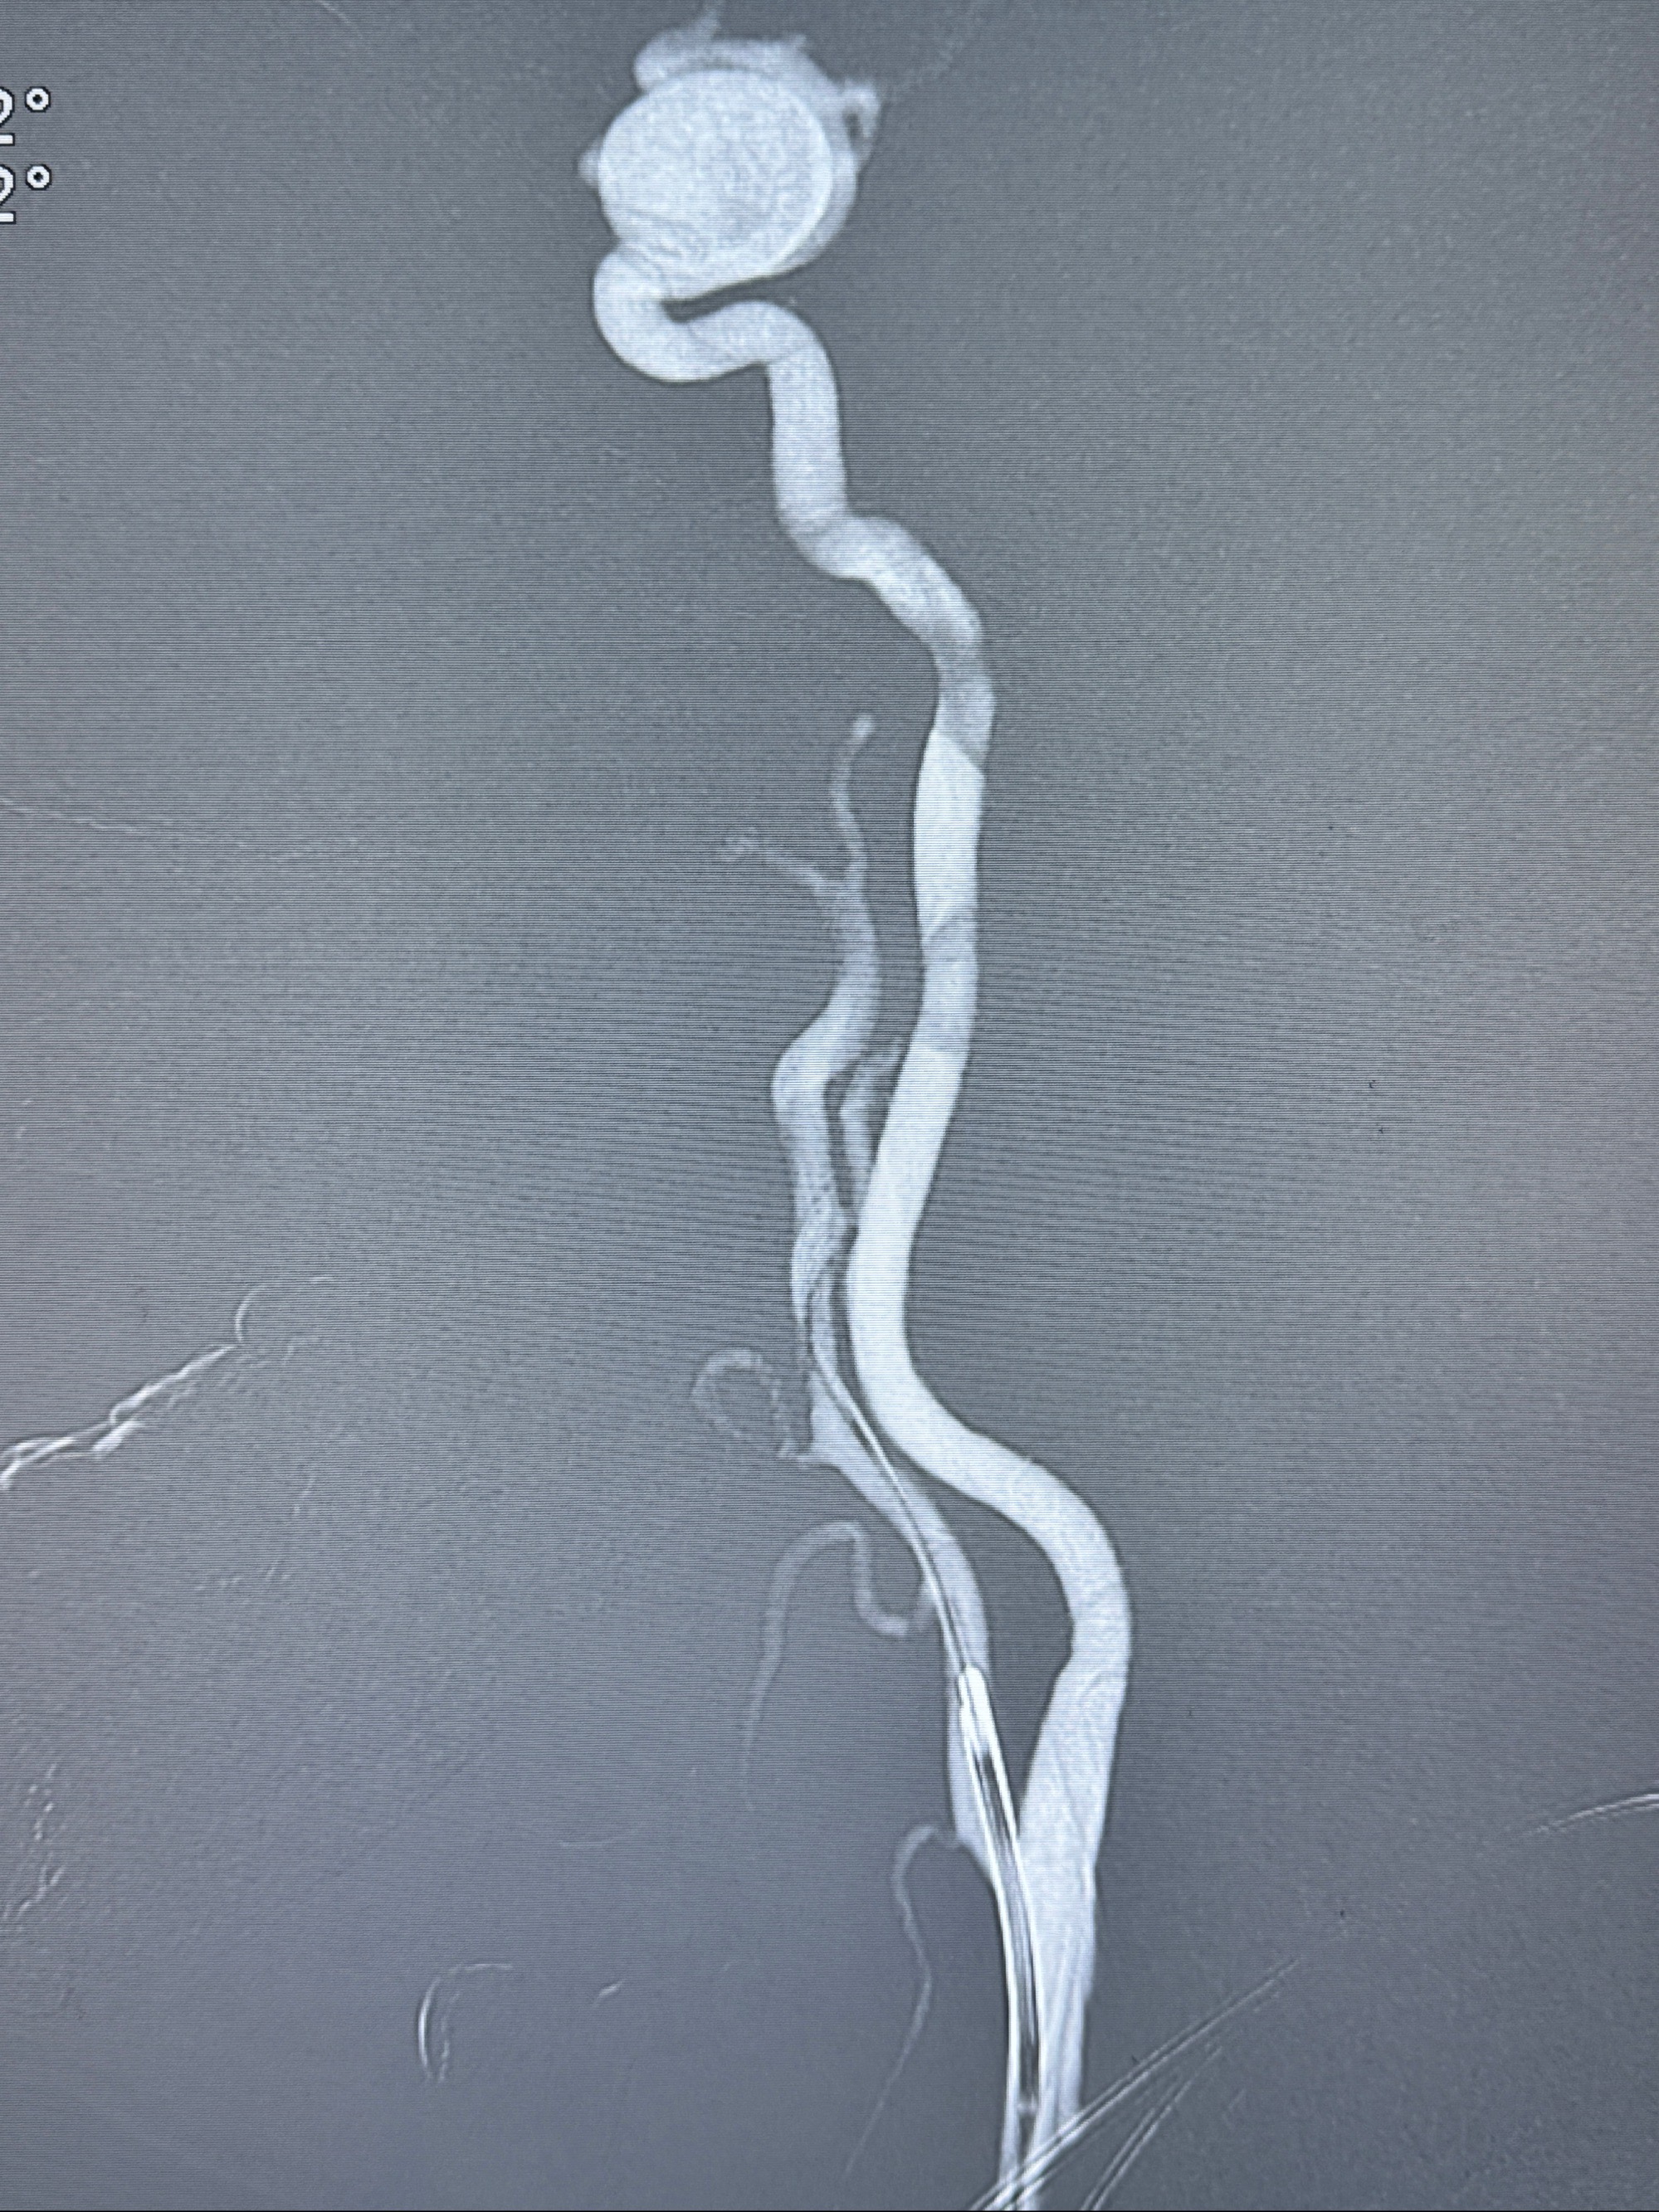

密网支架微导管在微导丝引导下超选择性插入右侧大脑中动脉

4.5-30mmTurbridge密网支架,于M1近心端打开

透视下支架释放满意

多角度显示支架打开情况

造影显示支架贴壁情况